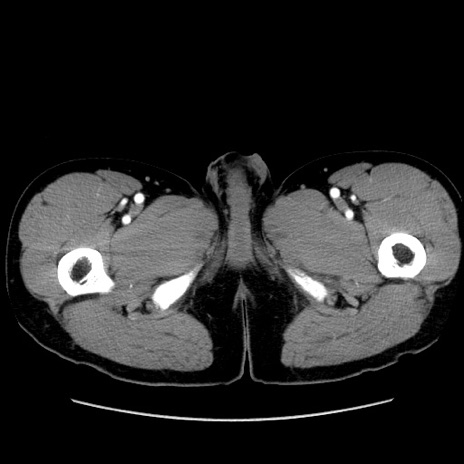

症例36(横断像)

【症例】20歳代 男性

【主訴】心窩部痛

【現病歴】今朝より上腹部痛あり。一旦軽快していたが再度出現したため救急要請。昨日夕に白身の魚を含む刺身を食べた。

【身体所見】BP 136/89mmHg、HR 74/min、BT 37.0℃、腹部:膨満、軟、心窩部に圧痛あり。反跳痛なし、筋性防御なし、腸雑音やや亢進あり。

【データ】WBC 17700、CRP 0.48